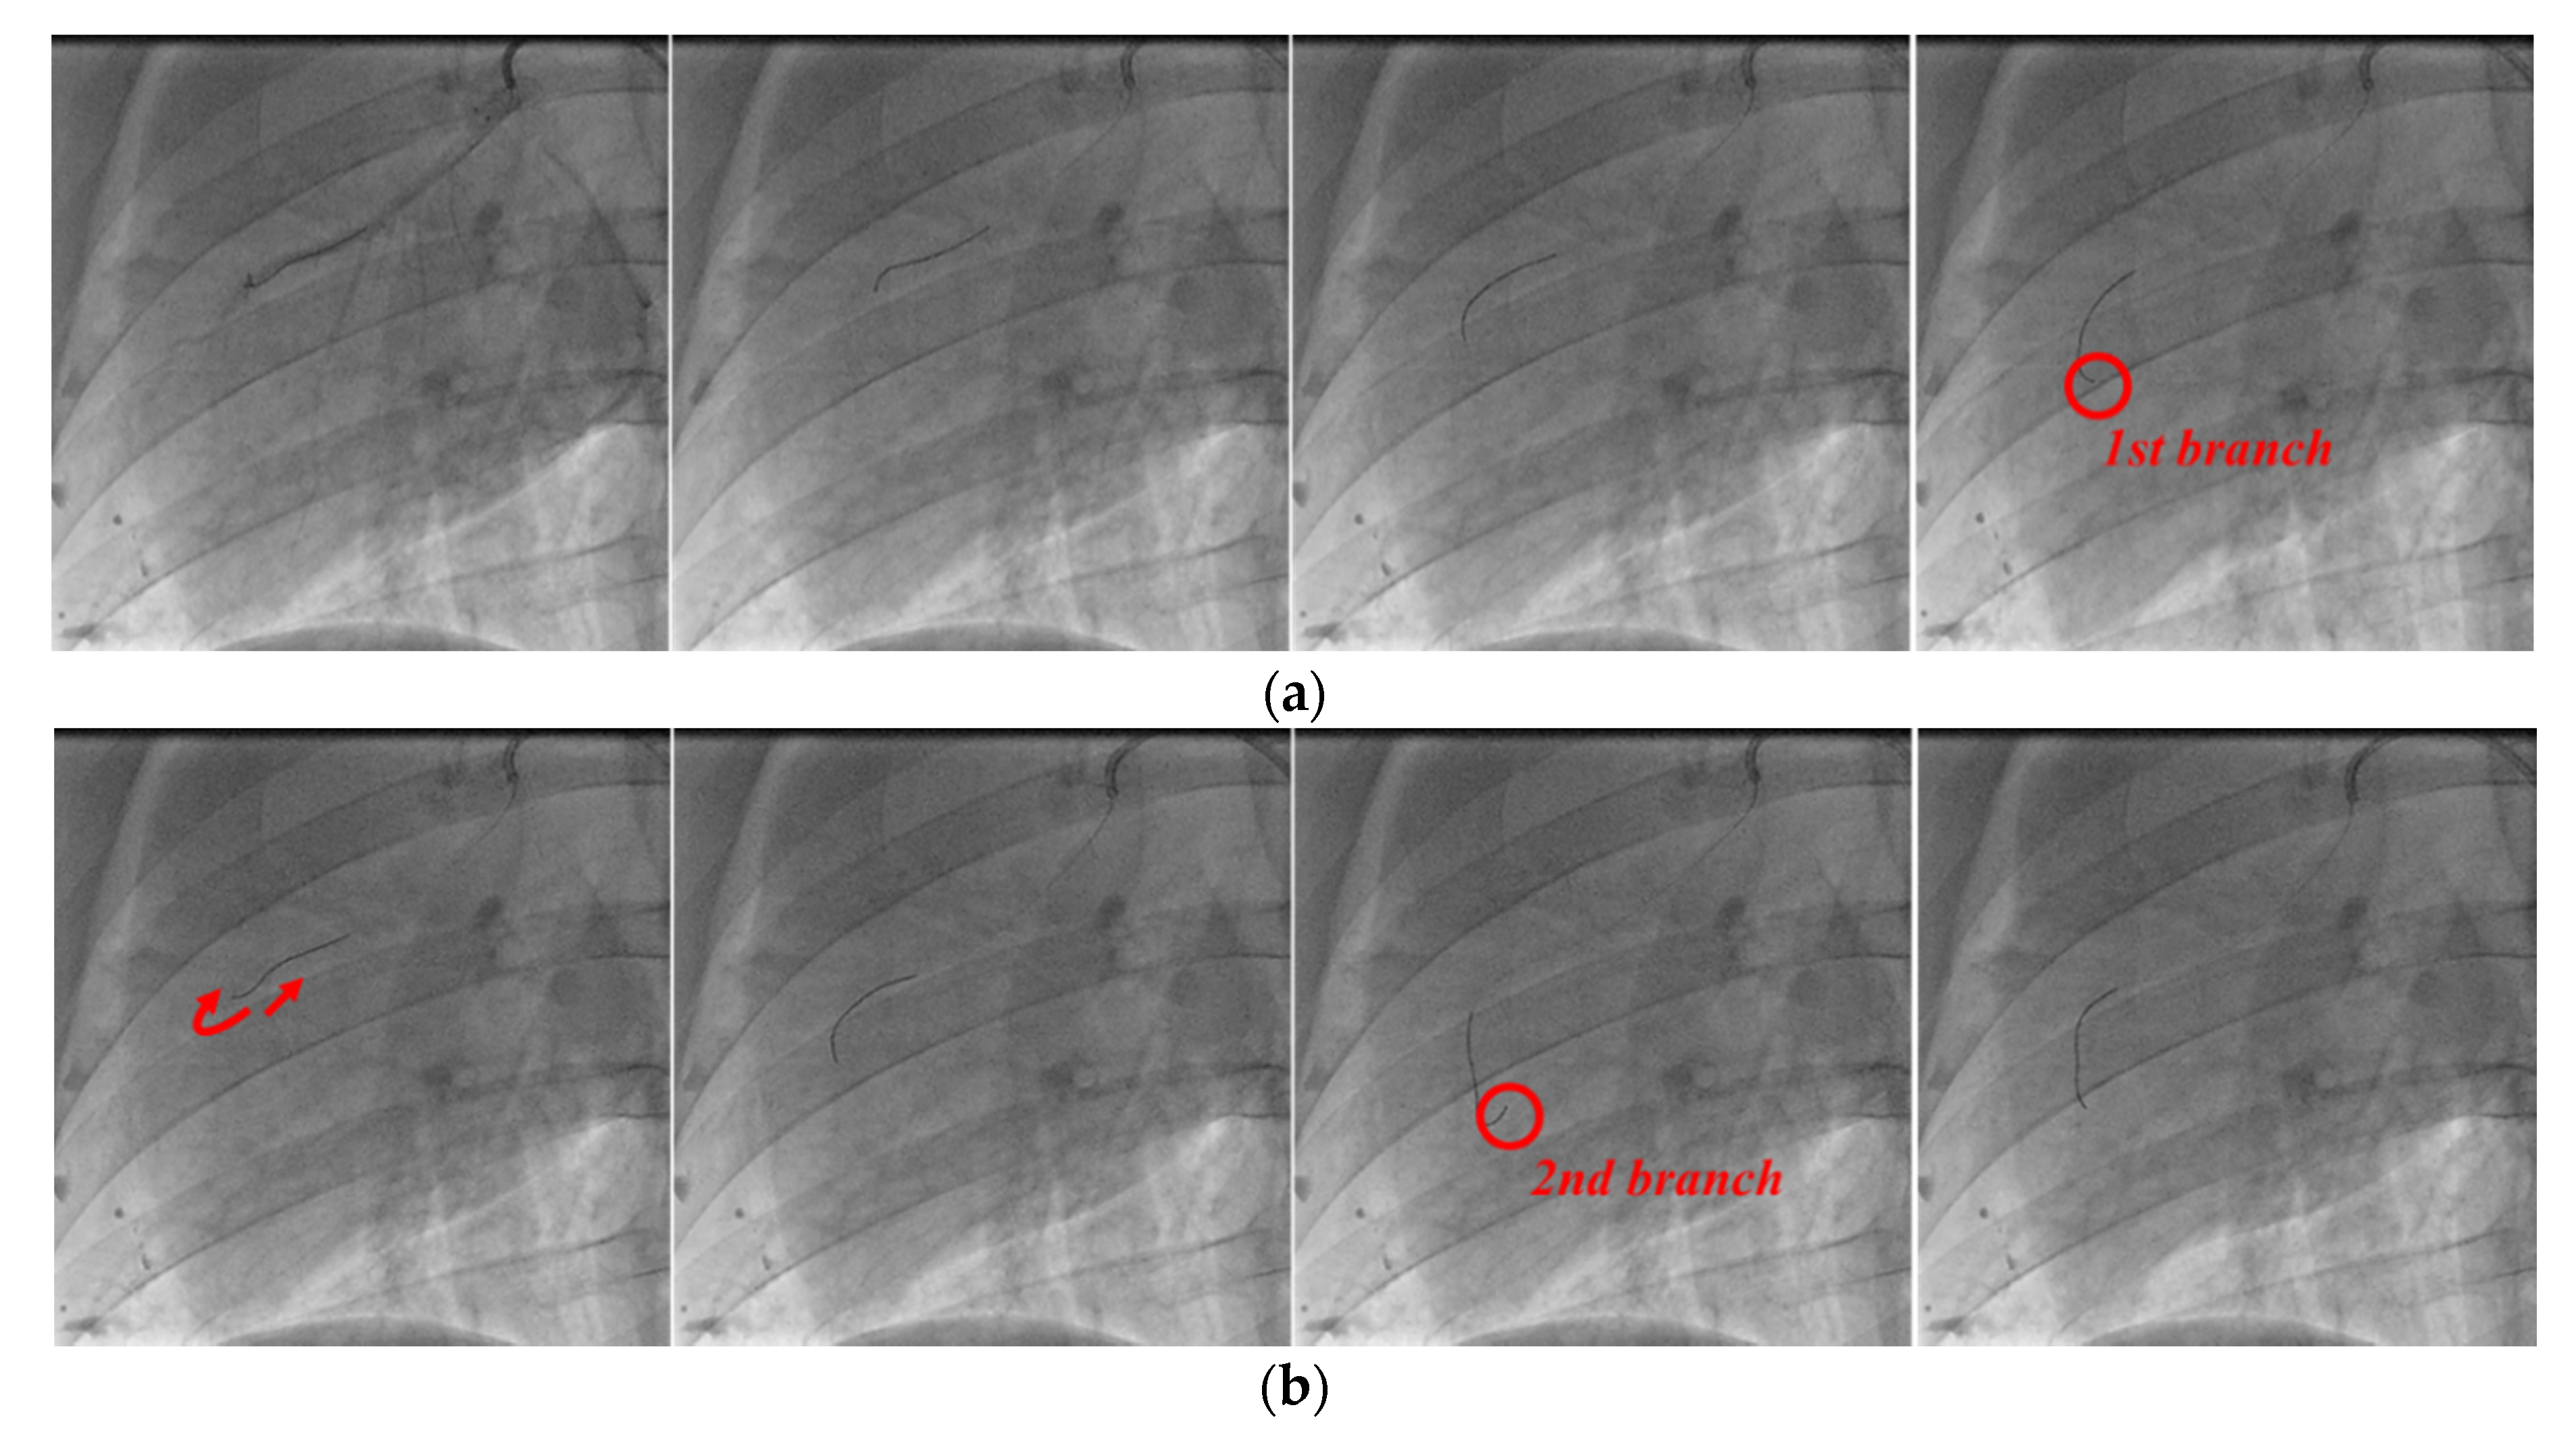

The angiography images of each stage in the process of guidewire advancement are shown in Figure 16. The guidewire was advanced, and it reached the first branch point, as shown in Figure 16a. Then, the guidewire was withdrawn from the first branch by moving it backward and rotating it, and it was advanced again to reach the second branch, as shown in Figure 16b. Finally, the guidewire was retracted and rotated again to exit from the second branch point, and then it was advanced to successfully reach the final target location, as shown in Figure 16c. In postoperative observation, the physician confirmed that there were no complications, such as perforation or bleeding.

Figure 16. Angiographic views of the right coronary artery of the pig. Process of inserting guidewire into (a) first branch, (b) second branch, and (c) final target.

Biosensors 11 00329 g016aBiosensors 11 00329 g016b